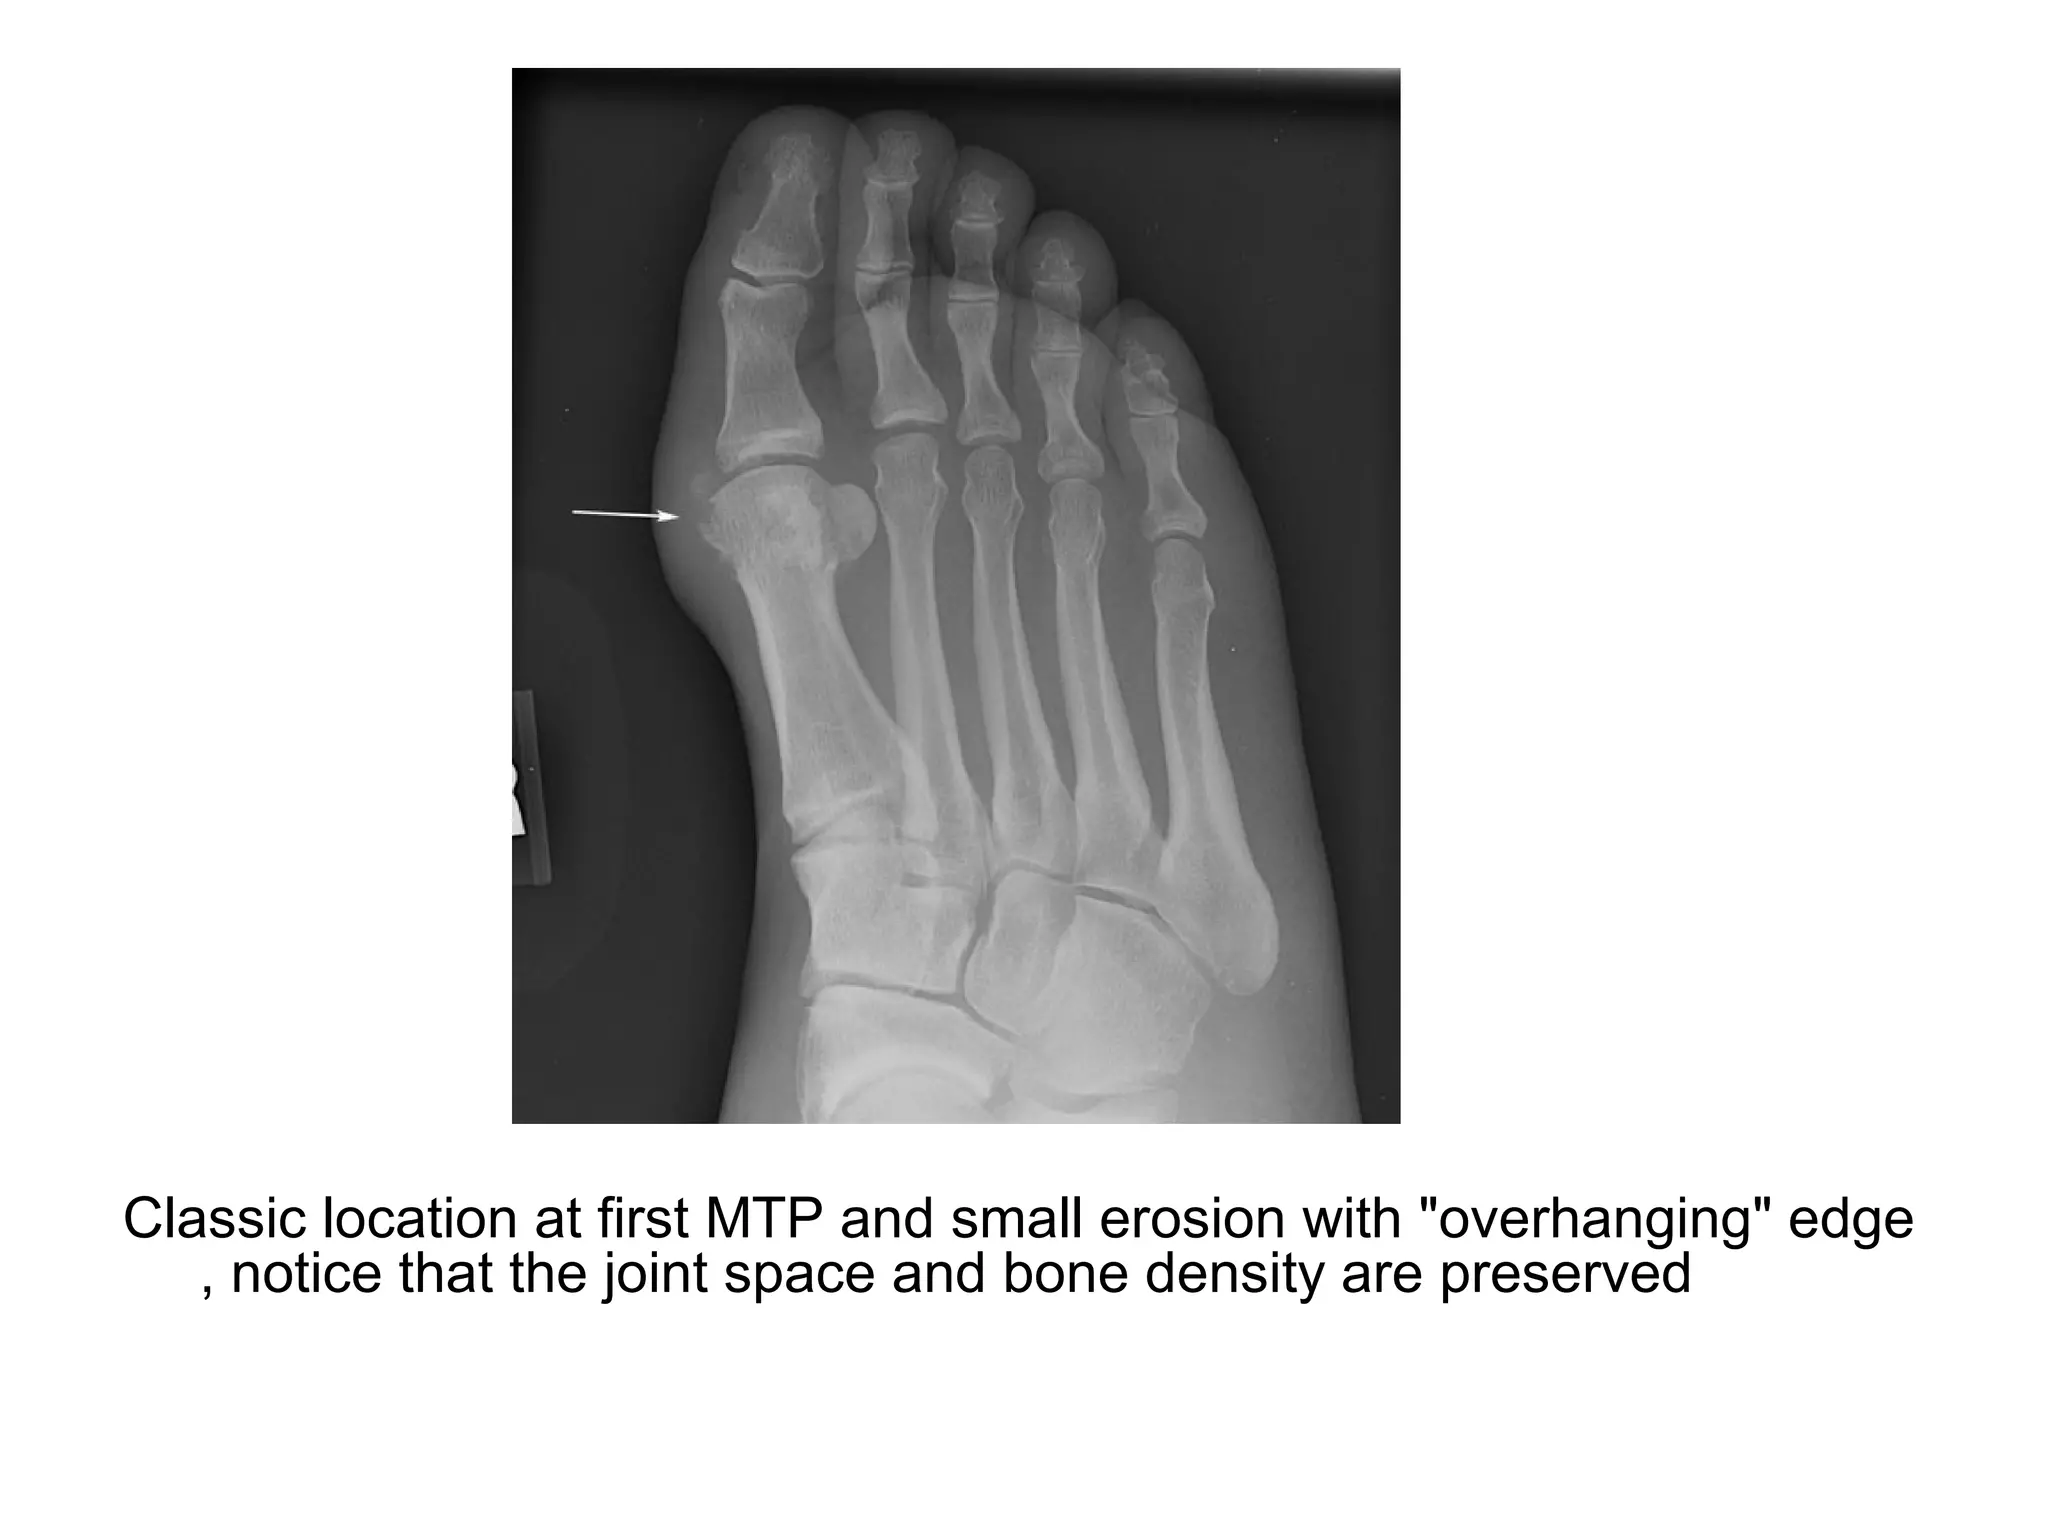

Classic location at first MTP and small erosion with "overhanging" edge

, notice that the joint space and bone density are preserved